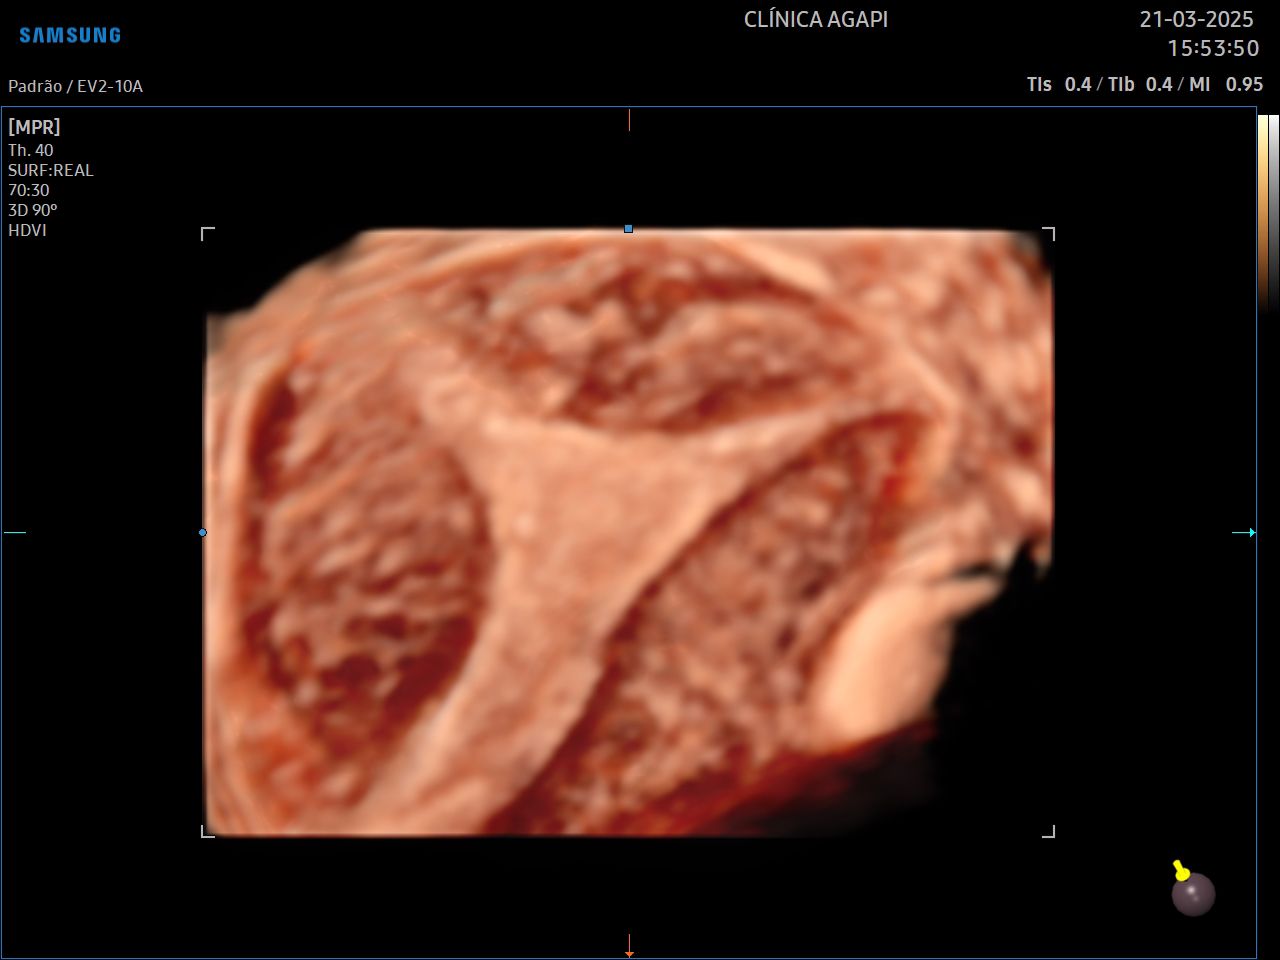

Ultrassonografia Ginecológica 3D/4D

Exame complementar à ultrassonografia transvaginal comum, que auxilia no diagnóstico de algumas malformações uterinas.